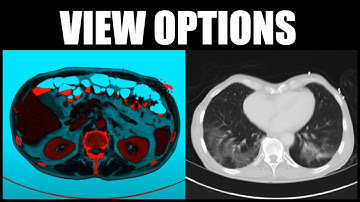

FireVoxel Tutorial 1: Basic Operations